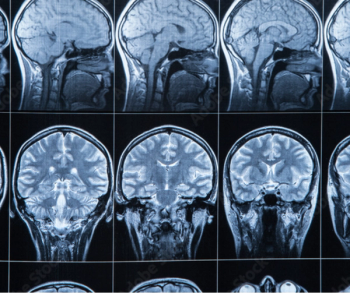

The advisory emphasizes that the computer-aided triage and notification (CADt) devices, many of which incorporate artificial intelligence (AI) or machine learning technology, are intended to aid radiologists in prioritizing the assessment of brain imaging that may reveal signs of large vessel occlusion (LVO).

The new artificial intelligence (AI) algorithm reportedly flags suspected cases of brain aneurysm and facilitates multidisciplinary care.